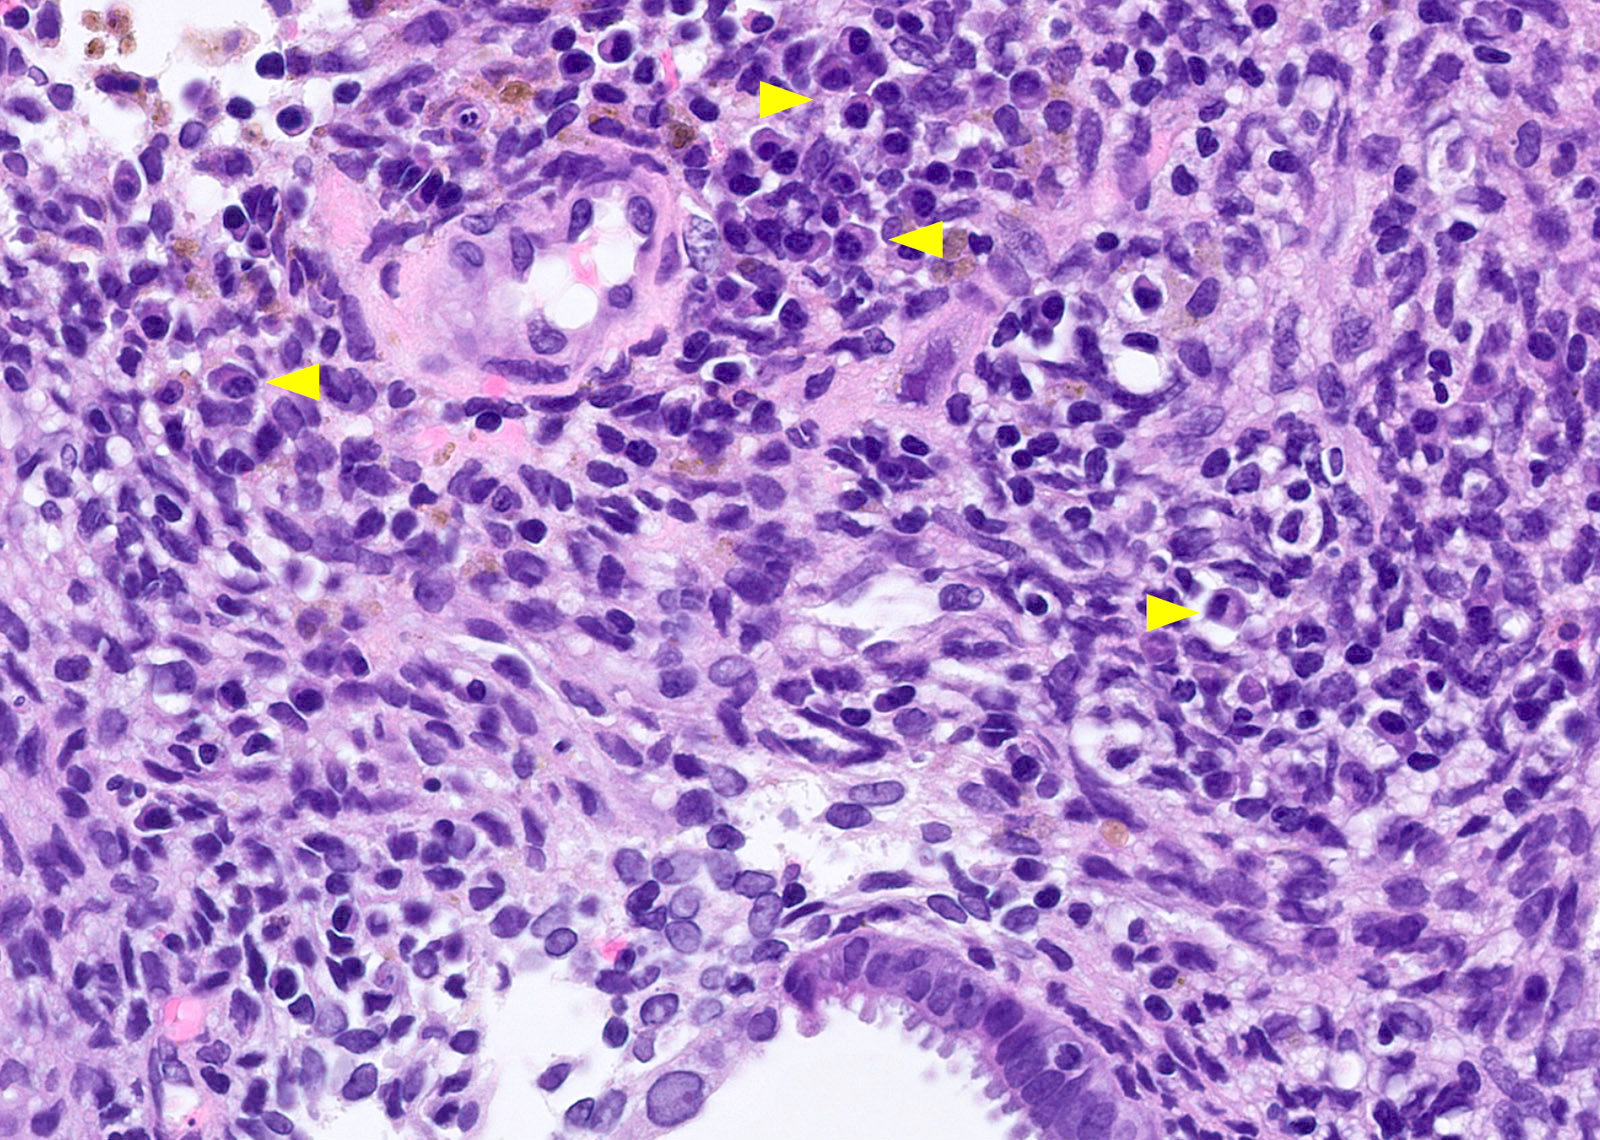

Microscopic (histologic) images

Contributed by Stephanie L. Skala, M.D. and Yuri Tachibana, M.D.

Chronic endometritis

Xanthogranulomatous endometritis

- Xanthogranulomatous endometritis

- Abundant foamy histiocytes, siderophages, neutrophils, plasma cells, lymphocytes

- With or without fibrosis, calcification